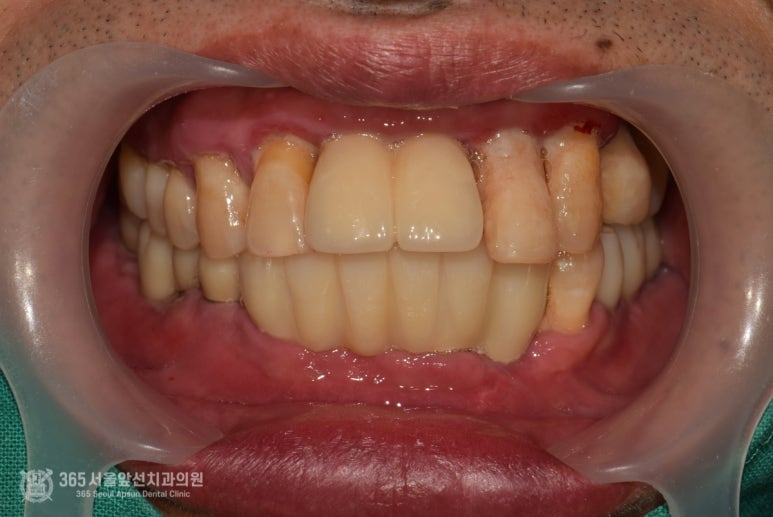

촬영일시: 2024.07.06. 구강스캐너를 사용하여 즉시보철물 제작을 위한 본을 뜹니다. 세상이 정말 편해졌습니다 ㅎㅎ 아래턱 뼈의 밀도가 나쁘지 않았기에 충분한 고정력을 얻을 수 있었고, 환자분의 바람대로 수술 후 즉시 임시치아를 해드릴 수 있었습니다. 촬영일시 : 2024.07.06. 수술 후 임시치아를 바로 연결해드리는 경우, 단단한 음식을 매우 조심하셔야 합니다. 임플란트가 충분히 고정력을 얻었더라도 아직 뼈와 완전하게 골융합되지 않았으므로 강한 저작력이 가해질 경우 임플란트가 빠질 수 있기 때문입니다. 환자분께 이러한 주의 사항을 충분히 드리고 주기적으로 체크하며 관리해드렸습니다ㅎㅎ 대략 4개월 정도 기간이 지난 후 최종보철물로 교체하여 완성해드렸습니다. 즉시 임시치아를 해드릴 경우 몇몇 임플란트가 빠질 수 있으나, 다행히 환자분께서 조심조심해서 식사를 해주시고 관리를 열심히 해주셔서 단 한개의 임플란트도 빠지지 않고 마무리해드릴 수 있었습니다 ^^ 촬영일시 : 2024.11.02. 완성 후 구강 내 모습입니다. 아래턱 치료가 마음에 드셔서 그런지 얼른 윗턱 임플란트 치료도 받고 싶어하십니다 ㅎㅎ 촬영일시: 2024.11.02. 오늘은 뼈이식을 동반한 발치즉시 임플란트 수술 및 즉시임시치아 제작까지 해드렸던 환자분의 증례를 공유해보았습니다. 뼈의 양이나 뼈의 질에 따라서 즉시임시치아는 불가능할 수도 있으니 의료진과 충분한 상의하에 만족스러운 치료를 받으시면 좋겠습니다 ㅎㅎ 이상, 도화역치과 365서울앞선치과였습니다. 더 좋은 증례로 찾아뵙겠습니다! ※ 365서울앞선치과의원의 모든 포스팅은 각 진료과 의료진이 직접 작성합니다. 365서울앞선치과의원 블로그의 임상 케이스 게시물은 환자분께 의학적으로 정확하고 상세한 정보를 드리기 위해 각 진료과 의료진이 직접 작성하며, 모든 증례 사진은 본원 의료진이 직접 시술한 증례를 촬영한 것으로, 의료법 제23조, 제56조에 의거하며 환자분의 동의를 얻어 포스팅에 사용하였습니다. 또한 해당 케이스는 본 환자분의 치료 결과이며, 환자 상태에 따라 치료의 결과는 달라질 수 있습니다. |